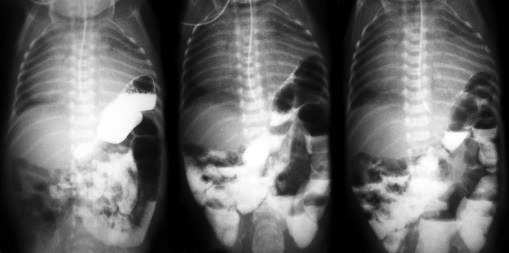

По УЗИ брюшной полости – без патологии. На рентгенографии желудочно-кишечного тракта (ЖКТ) с проходящим барием – петли кишечника определяются в правой половине грудной клетки. На 4-е сут проведена МСКТ легких, которая подтвердила диагноз правосторонней диафрагмальной грыжи, содержимое – петли кишечника. Ребенок прооперирован 17.05 – лапаротомия в правом подреберье, проведена пластика правого купола диафрагмы (щель Бохдалека) собственными тканями по методике «за ребро». Послеоперационный период протекал тяжело. Отмечалось «парадоксальное дыхание» с втяжением податливых мест грудной клетки на вдохе, вероятно, обусловленное врожденной патологией развития и иннервации диафрагмы, усугубленное гипоплазией правого легкого. На 4-е сут после операции – самостоятельное дыхание с дотацией кислорода через маску, гемодинамических расстройств не отмечено (рис. 7).

Рис. 7. Рентгенограмма органов грудной клетки, выполненная на 6-е сутки после операции.

На 13-е сут после операции отмечалась отрицательная респираторная динамика – усиление втяжения грудной клетки, ослабление дыхания слева. По рентгенограмме – подозрение на левостороннюю диафрагмальную грыжу (рис. 8). Ребенок переведен на ИВЛ, начата интенсивная терапия в режиме предоперационной подготовки. По эхокардиограмме – декстракардия, расширение правых отделов сердца. Отмечались постоянные срыгивания при кормлении, проведена декомпрессия желудка, «голодная пауза». На рентгенографии ЖКТ с проходящим контрастом – перемещение части желудка и петель кишечника в передние отделы левой грудной полости, затемнение левых легочных полей (рис. 9).